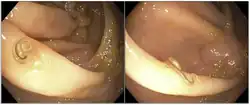

Há relatos na literatura do diagnóstico realizado de forma menos convencional, através do exame de colonoscopia, onde foram evidenciados parasitos inseridos no epitélio intestinal de um paciente [25].